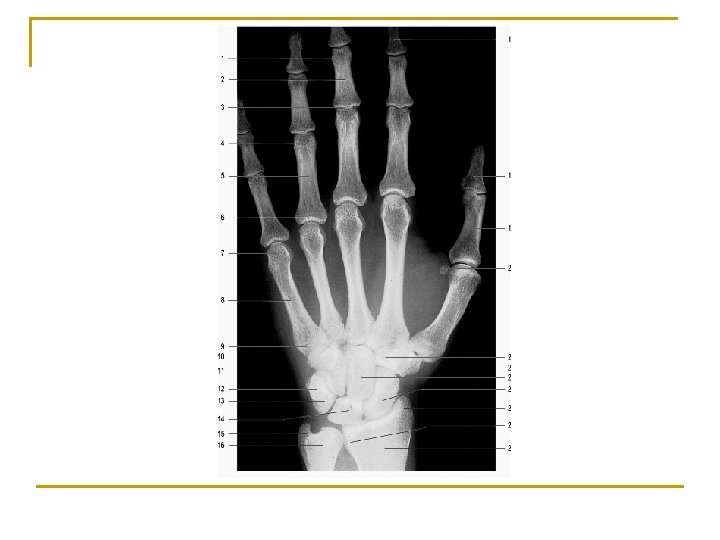

Carpal bones Proximal row ― (lateral to medial) n n Scaphoid Lunate Triquetral Pisiform Distal row ― (lateral to medial) n n Trapezium Trapezoid Capitate Hamate

Carpal bones H. C. Tq. P. Td. Tm. L. scaphoid, lunate, triquetral and pisiform trapezium, trapezoid, capitate and hamate S.

Metacarpal bones n n Numbered one to five from thumb to little finger Structure of each q q q base (proximally) Shaft head (distally)

Phalanges of fingers n n Consist of 14 ―two for first digit (thumb) and three for each of other four digits Structure of each q q base (proximally) Shaft trochlea of phalanx (distally) tuberosity of distal phalanx